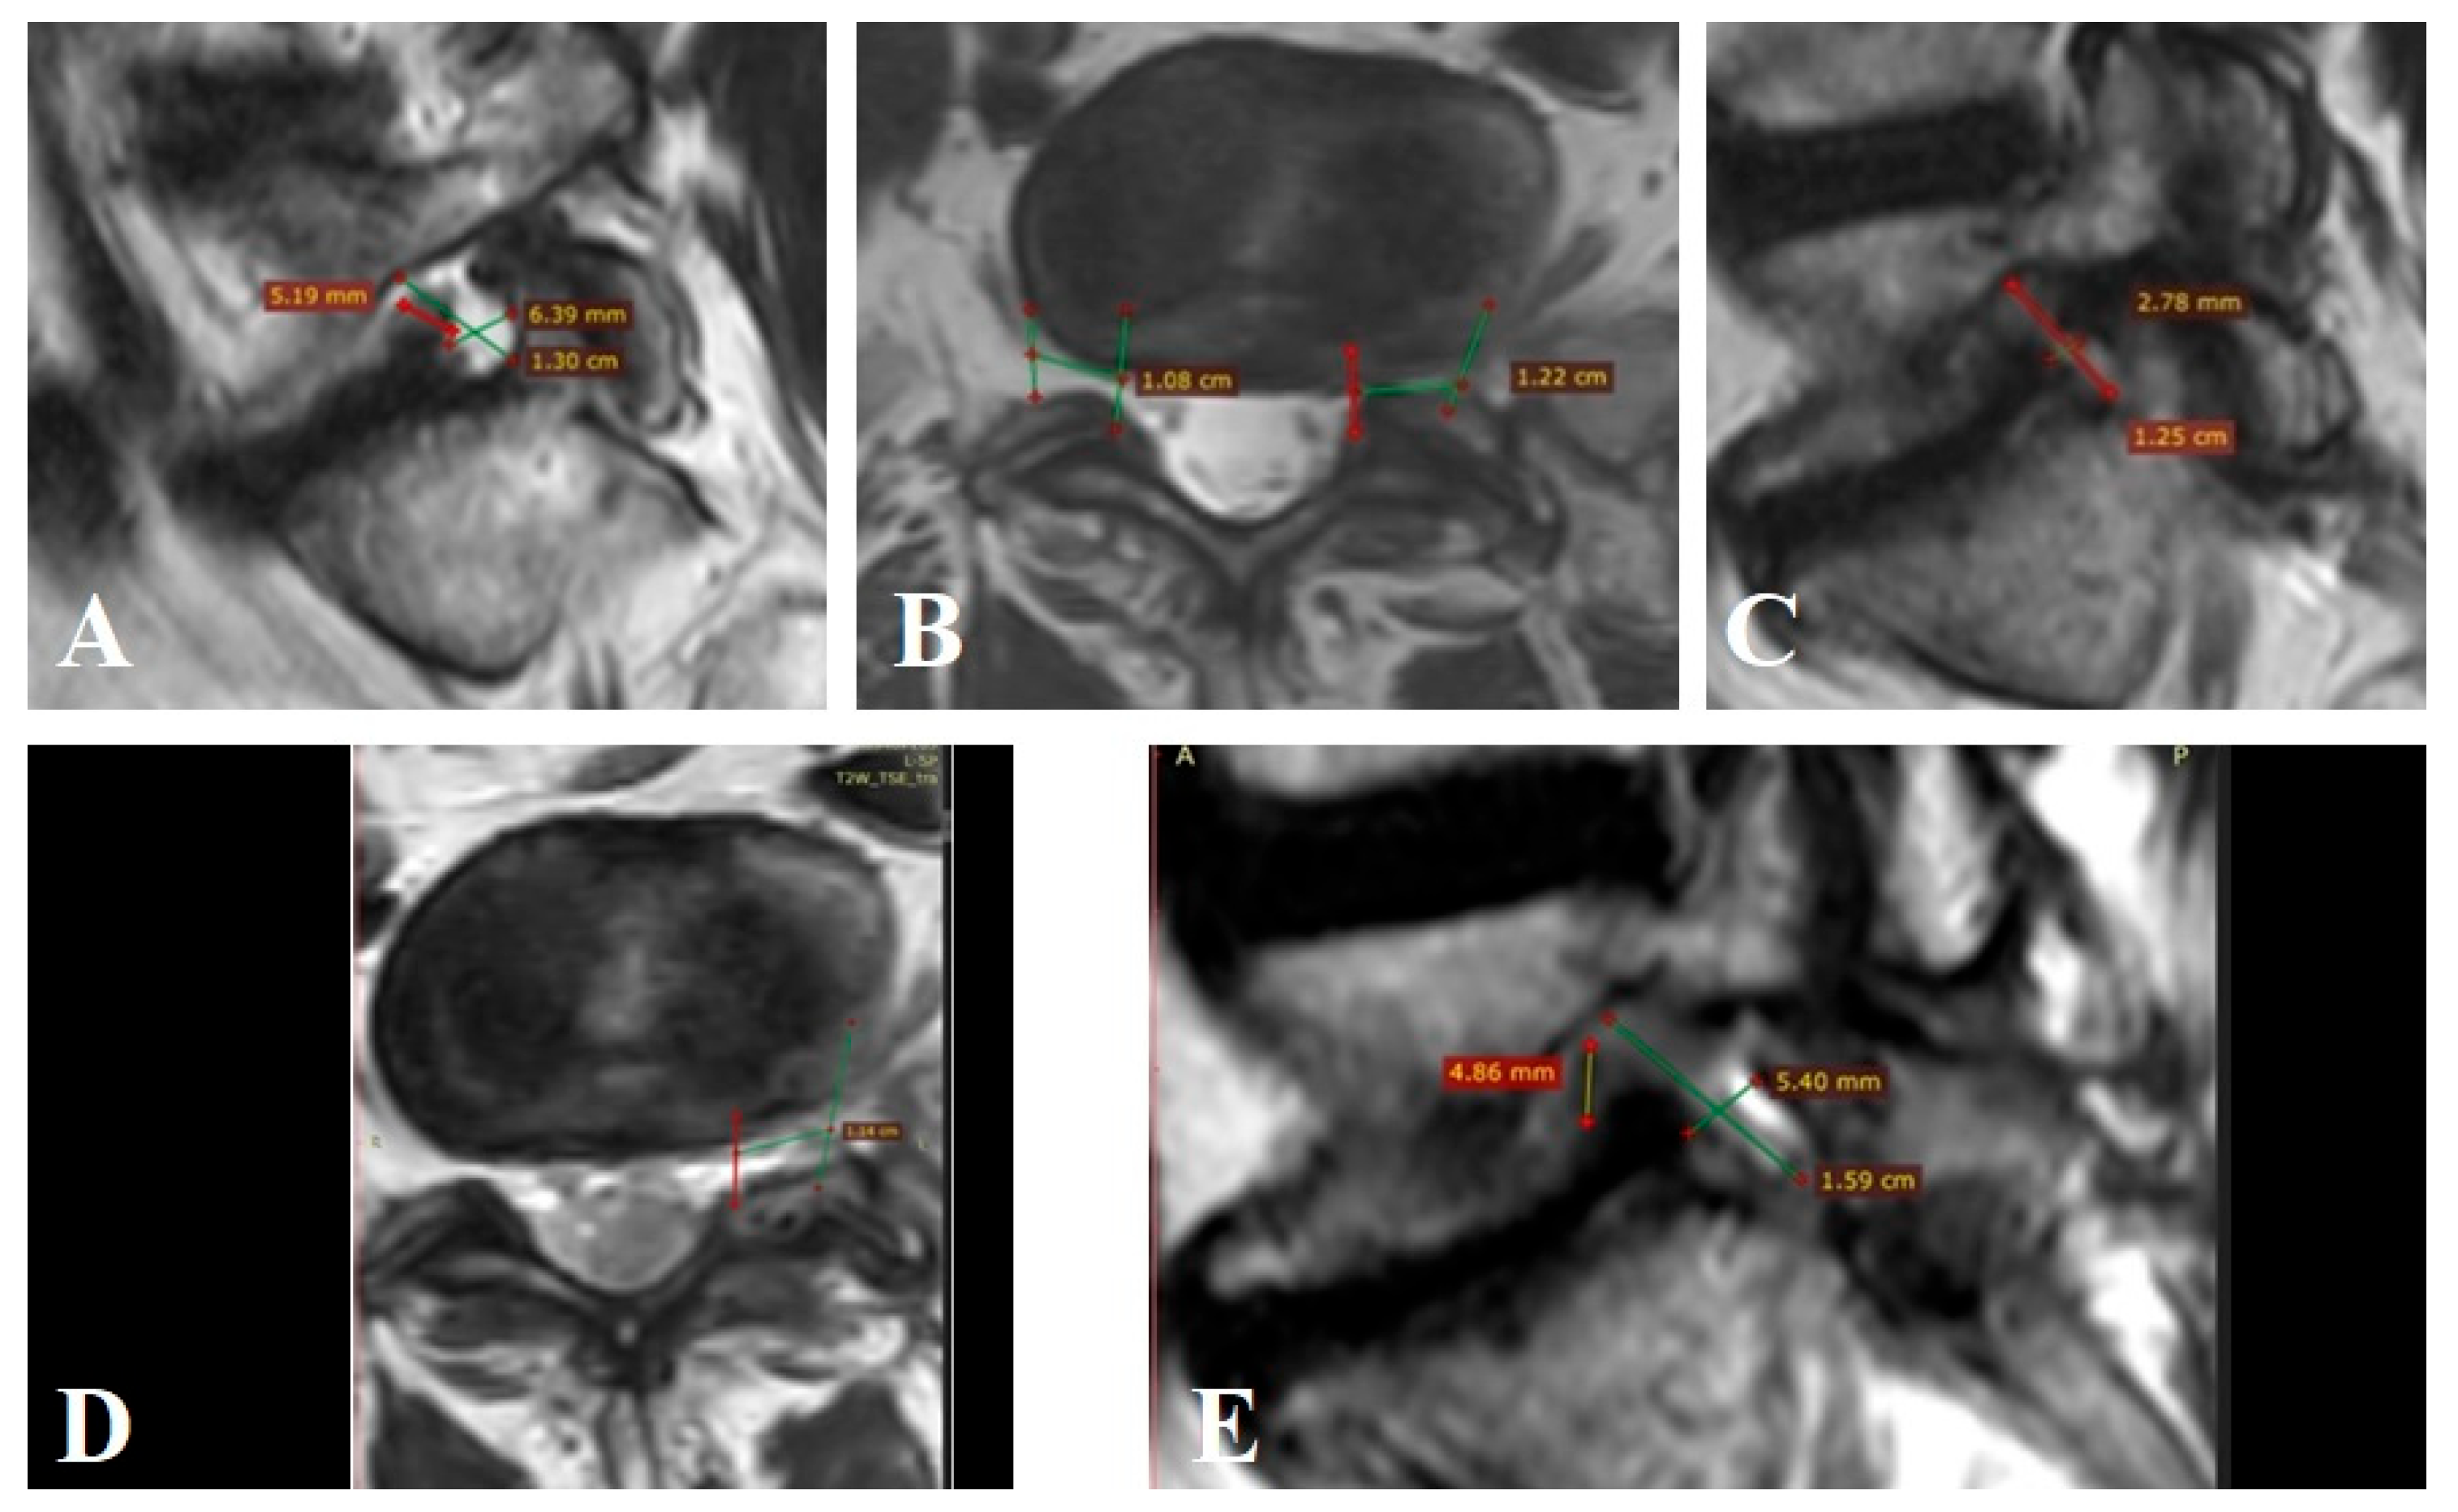

Patient n° 2 is a 55-year-old male, reported severe intermittent lumbar pain radiating to the right lower limb, unresponsive to three months of conservative therapy. VAS scores were 8 cm (leg) and 6 cm (back). Segmental instability was rated at 6 points per White–Panjabi criteria, and ODI was 55. MRI showed Grade 3 foraminal stenosis (Lee). On the right L4–L5 level, FC volume was 524.9 mm3, nerve volume 305.5 mm3, with 58.1% occupancy (Figure A2A). On the left, FC volume was 1492.5 mm3, nerve volume 305.2 mm3, and occupancy 20.85%. The patient underwent open foraminotomy, root decompression, and transforaminal lumbar interbody fusion (TLIF) at L4–L5. Postoperative FC volume on the right was 1638.1 mm3, nerve volume 305.8 mm3, and occupancy decreased to 18.6% (Figure A2B,C), representing a 68.0% increase in FC volume. On the left, postoperative FC volume remained 1492.5 mm3 with occupancy at 20.4% (Figure A2B,C). Pain decreased to 1.8 cm in the leg and 2 cm in the back. ODI improved to 19 at 12 months.

Figure A2.

MRI of patient n° 2.